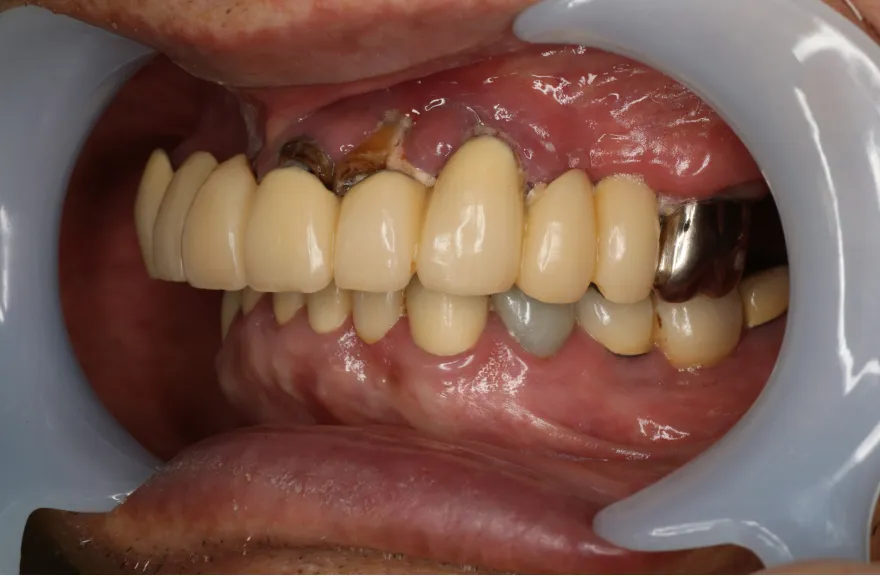

既にインプラント治療がなされており、使えるインプラントを使いながら足りないところにインプラントフィクスチャーを埋入し、噛み合わせを再構築する必要がある方でした。

上の前歯、右上の奥歯のインプラントはもう既に使える状態ではなく、また年月を経てすり減ってしまった下の前歯は噛み合わせを再構築する上で利用が難しい状況でした。

年齢を考えると、今回の治療で歯科治療を終えてしまい、残りの人生においてはメンテナンスのみで歯科へ通う状況を作りきってしまうことが求められました。

以上より、潔く残っている歯牙は抜去させていただき、上下をインプラントフィクスチャーによって固定式の歯を入れることとしました。 - 治療のリスク